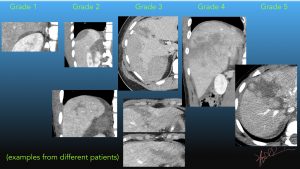

Liver Injury grading – Art of Surgery

Examples of AAST liver injury grading on CT. A A 17-year-old male with ...